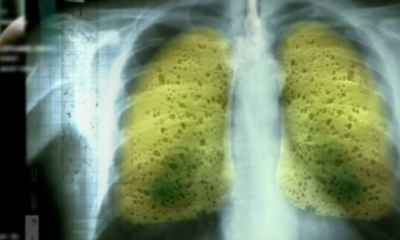

Βόμβα Υγείας: Αυτό Είναι το Απίθανο Ρόφημα που Εξαφανίζει Πίσσα και Νικοτίνη από τα Πνευμόνια!

21 Μαρτίου 2018Ποιο το απίθανο ρόφημα που θα εξαφανίσει την πίσσα και νικοτίνη από τα πνευμόνια; Οι καπνιστές,...